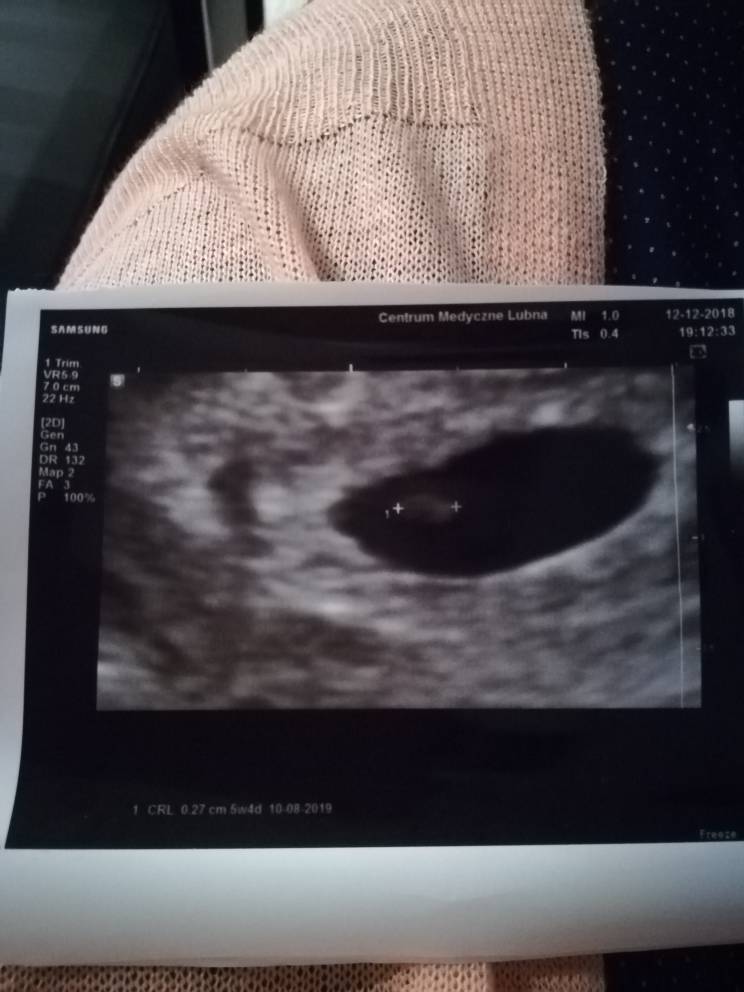

To dobrze, że wszystko ok. Ja byłam na wizycie w 6 tygodniu ciąży według usg dokładnie 5t4d i coś już lekarz dojrzał, choć mówił, że rewelacji nie ma. Takie zdjęcie dostałam: